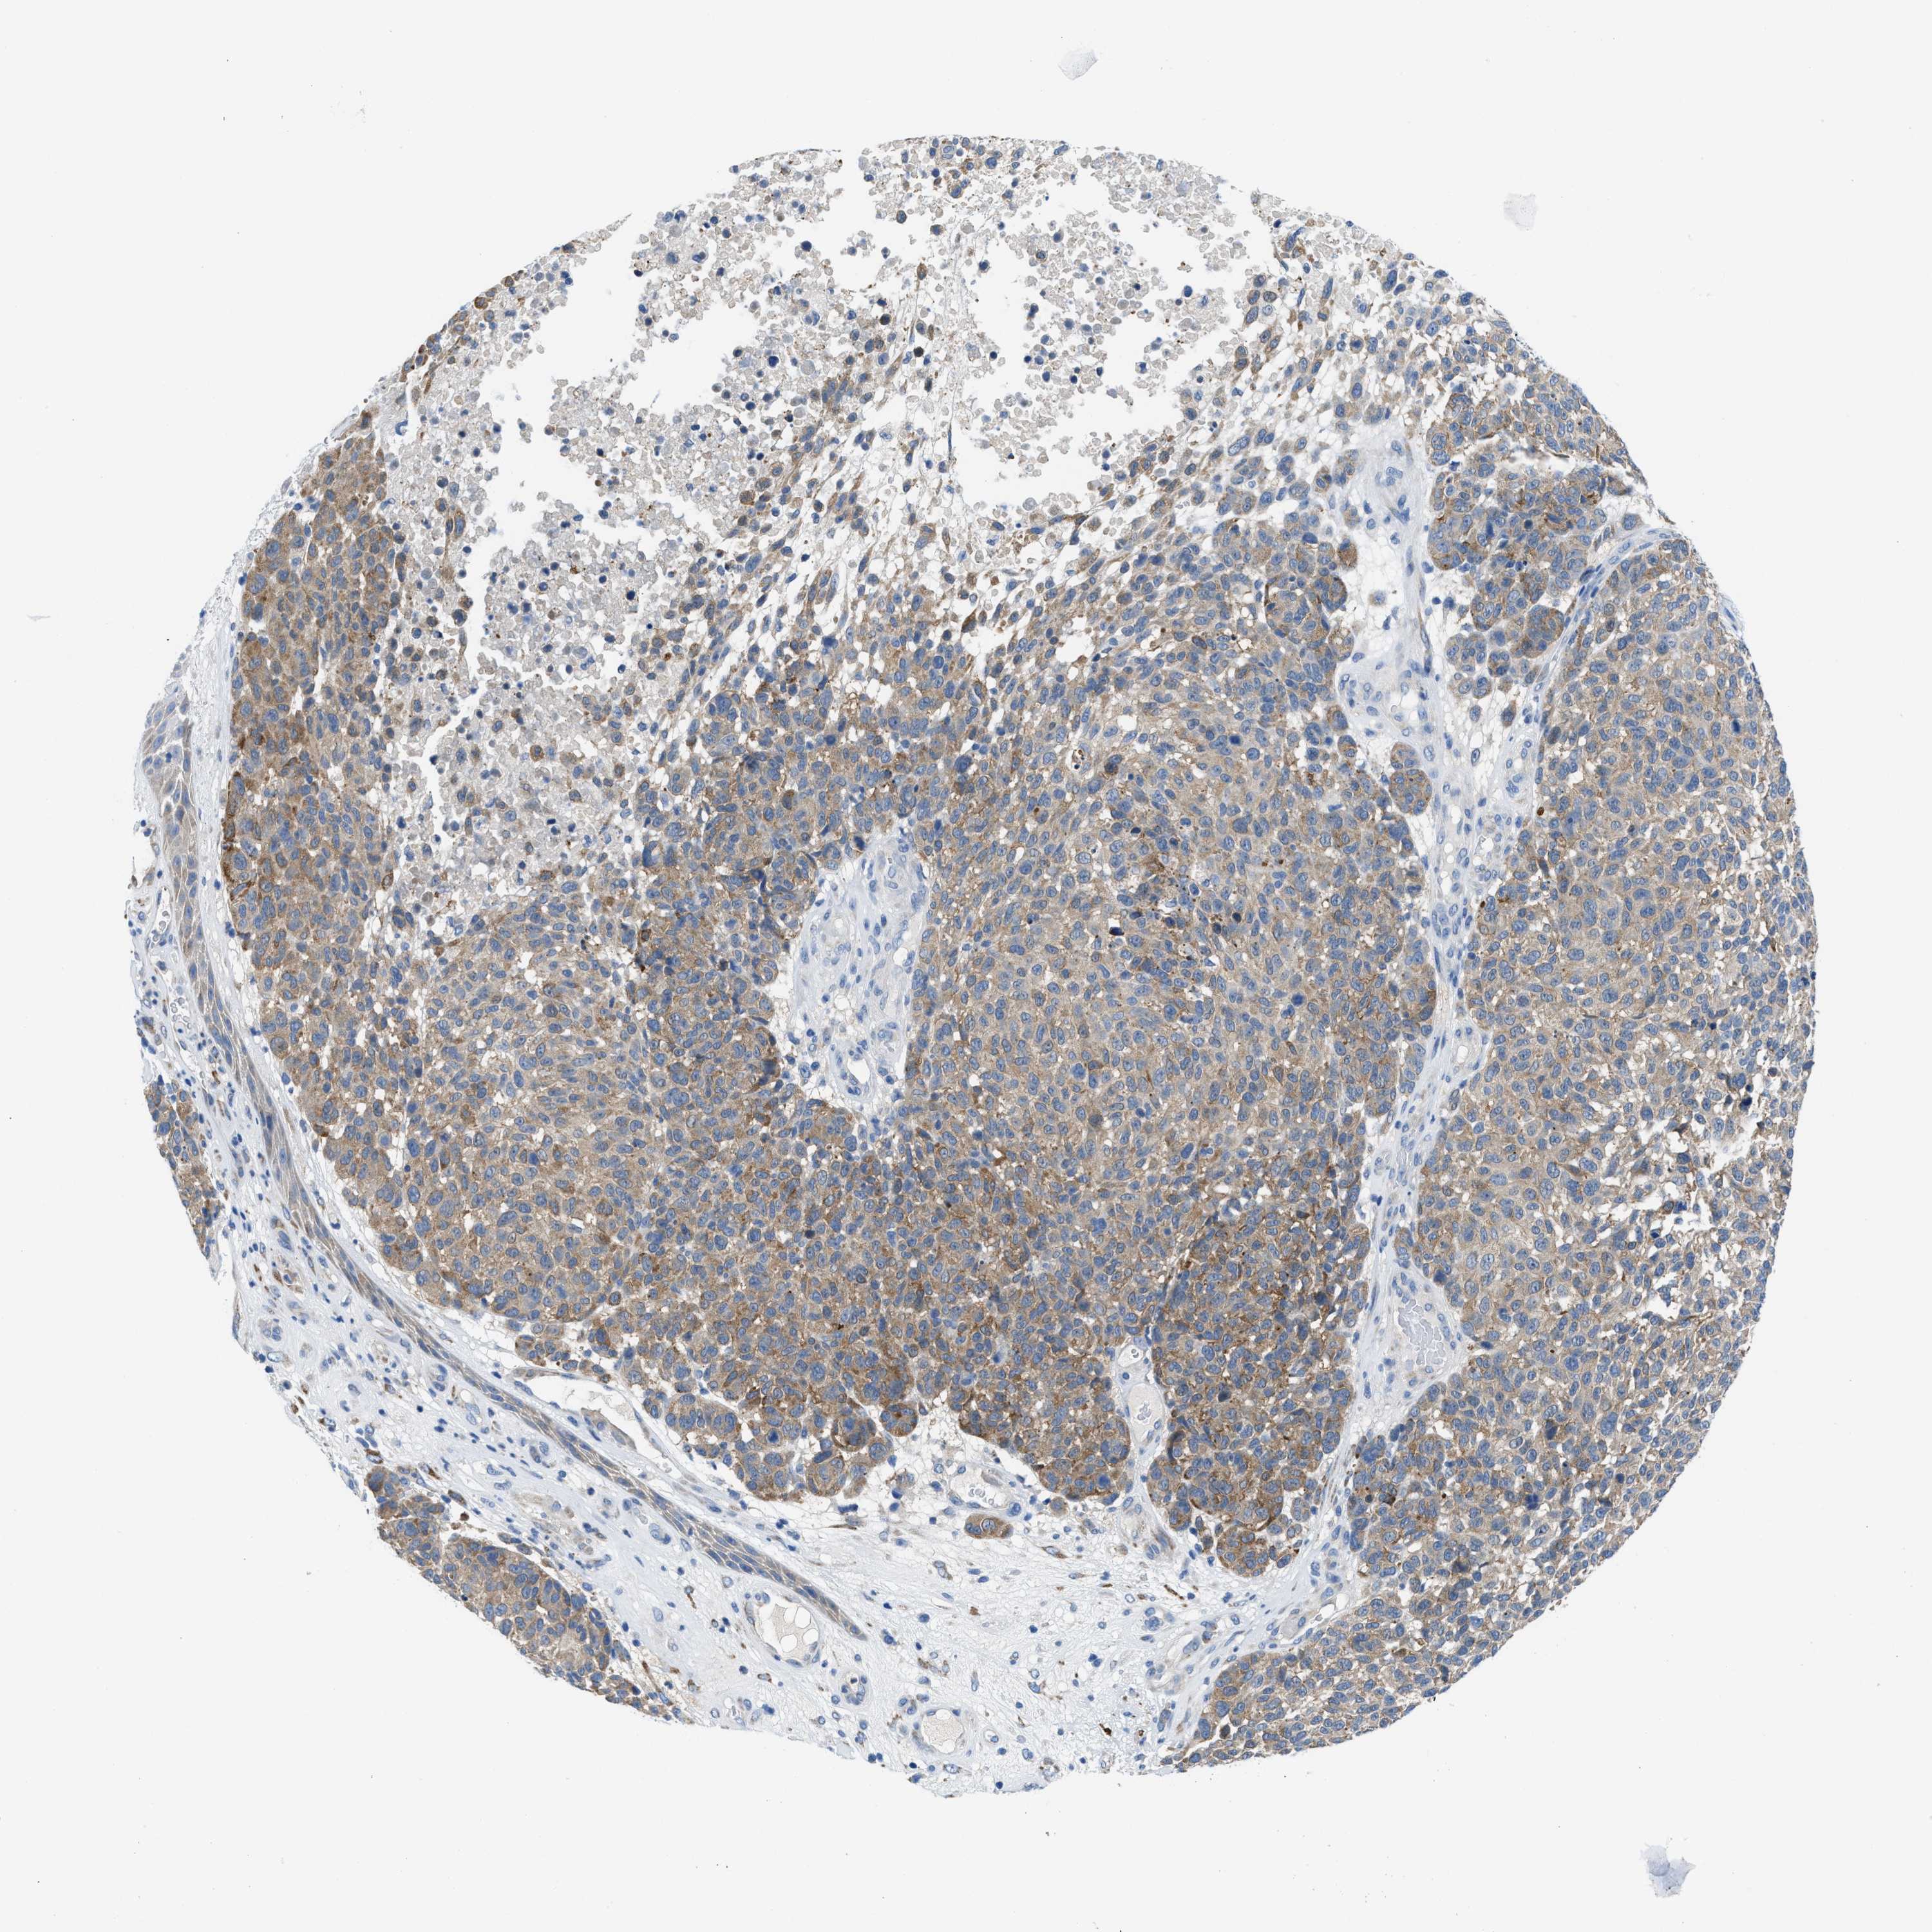

MELANOMA - Protein expressioni

A mouse-over function shows sample information and annotation data. Click on an image to view it in a full screen mode. Samples can be filtered based on level of antibody staining by selecting one or several of the following categories: high, medium, low and not detected. The assay and annotation is described here.

Note that samples used for immunohistochemistry by the Human Protein Atlas do not correspond to samples in the TCGA dataset.

Antibody stainingi

Antibody staining in the annotated cell types in the current human tissue is reported as not detected, low, medium, or high, based on conventional immunohistochemistry profiling in selected tissues. This score is based on the combination of the staining intensity and fraction of stained cells.

Each image is clickable and will lead to virtual microscopy that enables deeper exploration of all samples and also displays staining intensity scores, fraction scores and subcellular localization as well as patient and tissue information for each sample.

Antibody HPA018525

Staining

High

Medium

Low

Not detected

Intensity

Strong

Moderate

Weak

Negative

Quantity

>75%

75%-25%

<25%

None

Location

Nuclear

Cytoplasmic/membranous

Cytoplasmic/membranous,nuclear

Malignant melanoma, NOS

Malignant melanoma, Metastatic site